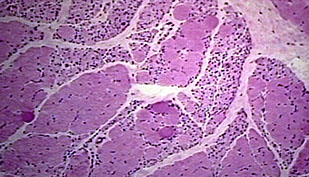

Inflammatory Myopathies

Lymphocytic infiltrates, fiber necrosis, regeneration

- Dermatomyositis: perifascicular fiber atrophy due to small

vessel vasculitis due to CD4-reactive T-cells. Best response to

steroids.

- Polymyositis: no perifascicular atrophy; Direct attack on muscle by CD8-reactive cytotoxic T-cells. Intermediate response to steroids.

Dermatomyositis (DM)

Inflammatory myopathy c generalized malaise and prox weakness

Micro: ab mediated damage to BV's results in perifascicular inflam/atrophy; may also see lymphocytic vascullitis

*** the perifascicular inflam is closer to the skin, which gives it the skin sx (not seen in PM, which is endomysial)***

Polymyositis (PM)

Micro: cell-mediated invasion of viable myofibers by CD8>4 lymphs --> endomysial inflam

- no vasculitis and no perifascicular atrophy